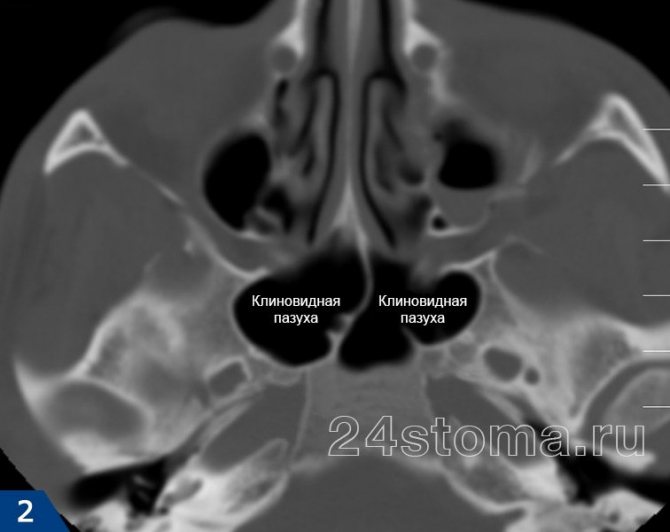

Для диагностики сфеноидита необходимо выполнение Компьютерной томографии (КТ) пазух носа.

КТ — исследование пазухи с помощью рентгеновского излучения. КТ позволяет выявить аномалии синуса, степень поражения слизистой. При исследовании с помощью КТ определяется уровень гноя в пазухе.

Ещё более информативным методом диагностики является МРТ — она выявляет послойные поражения, которые могут быть не замечены на КТ.